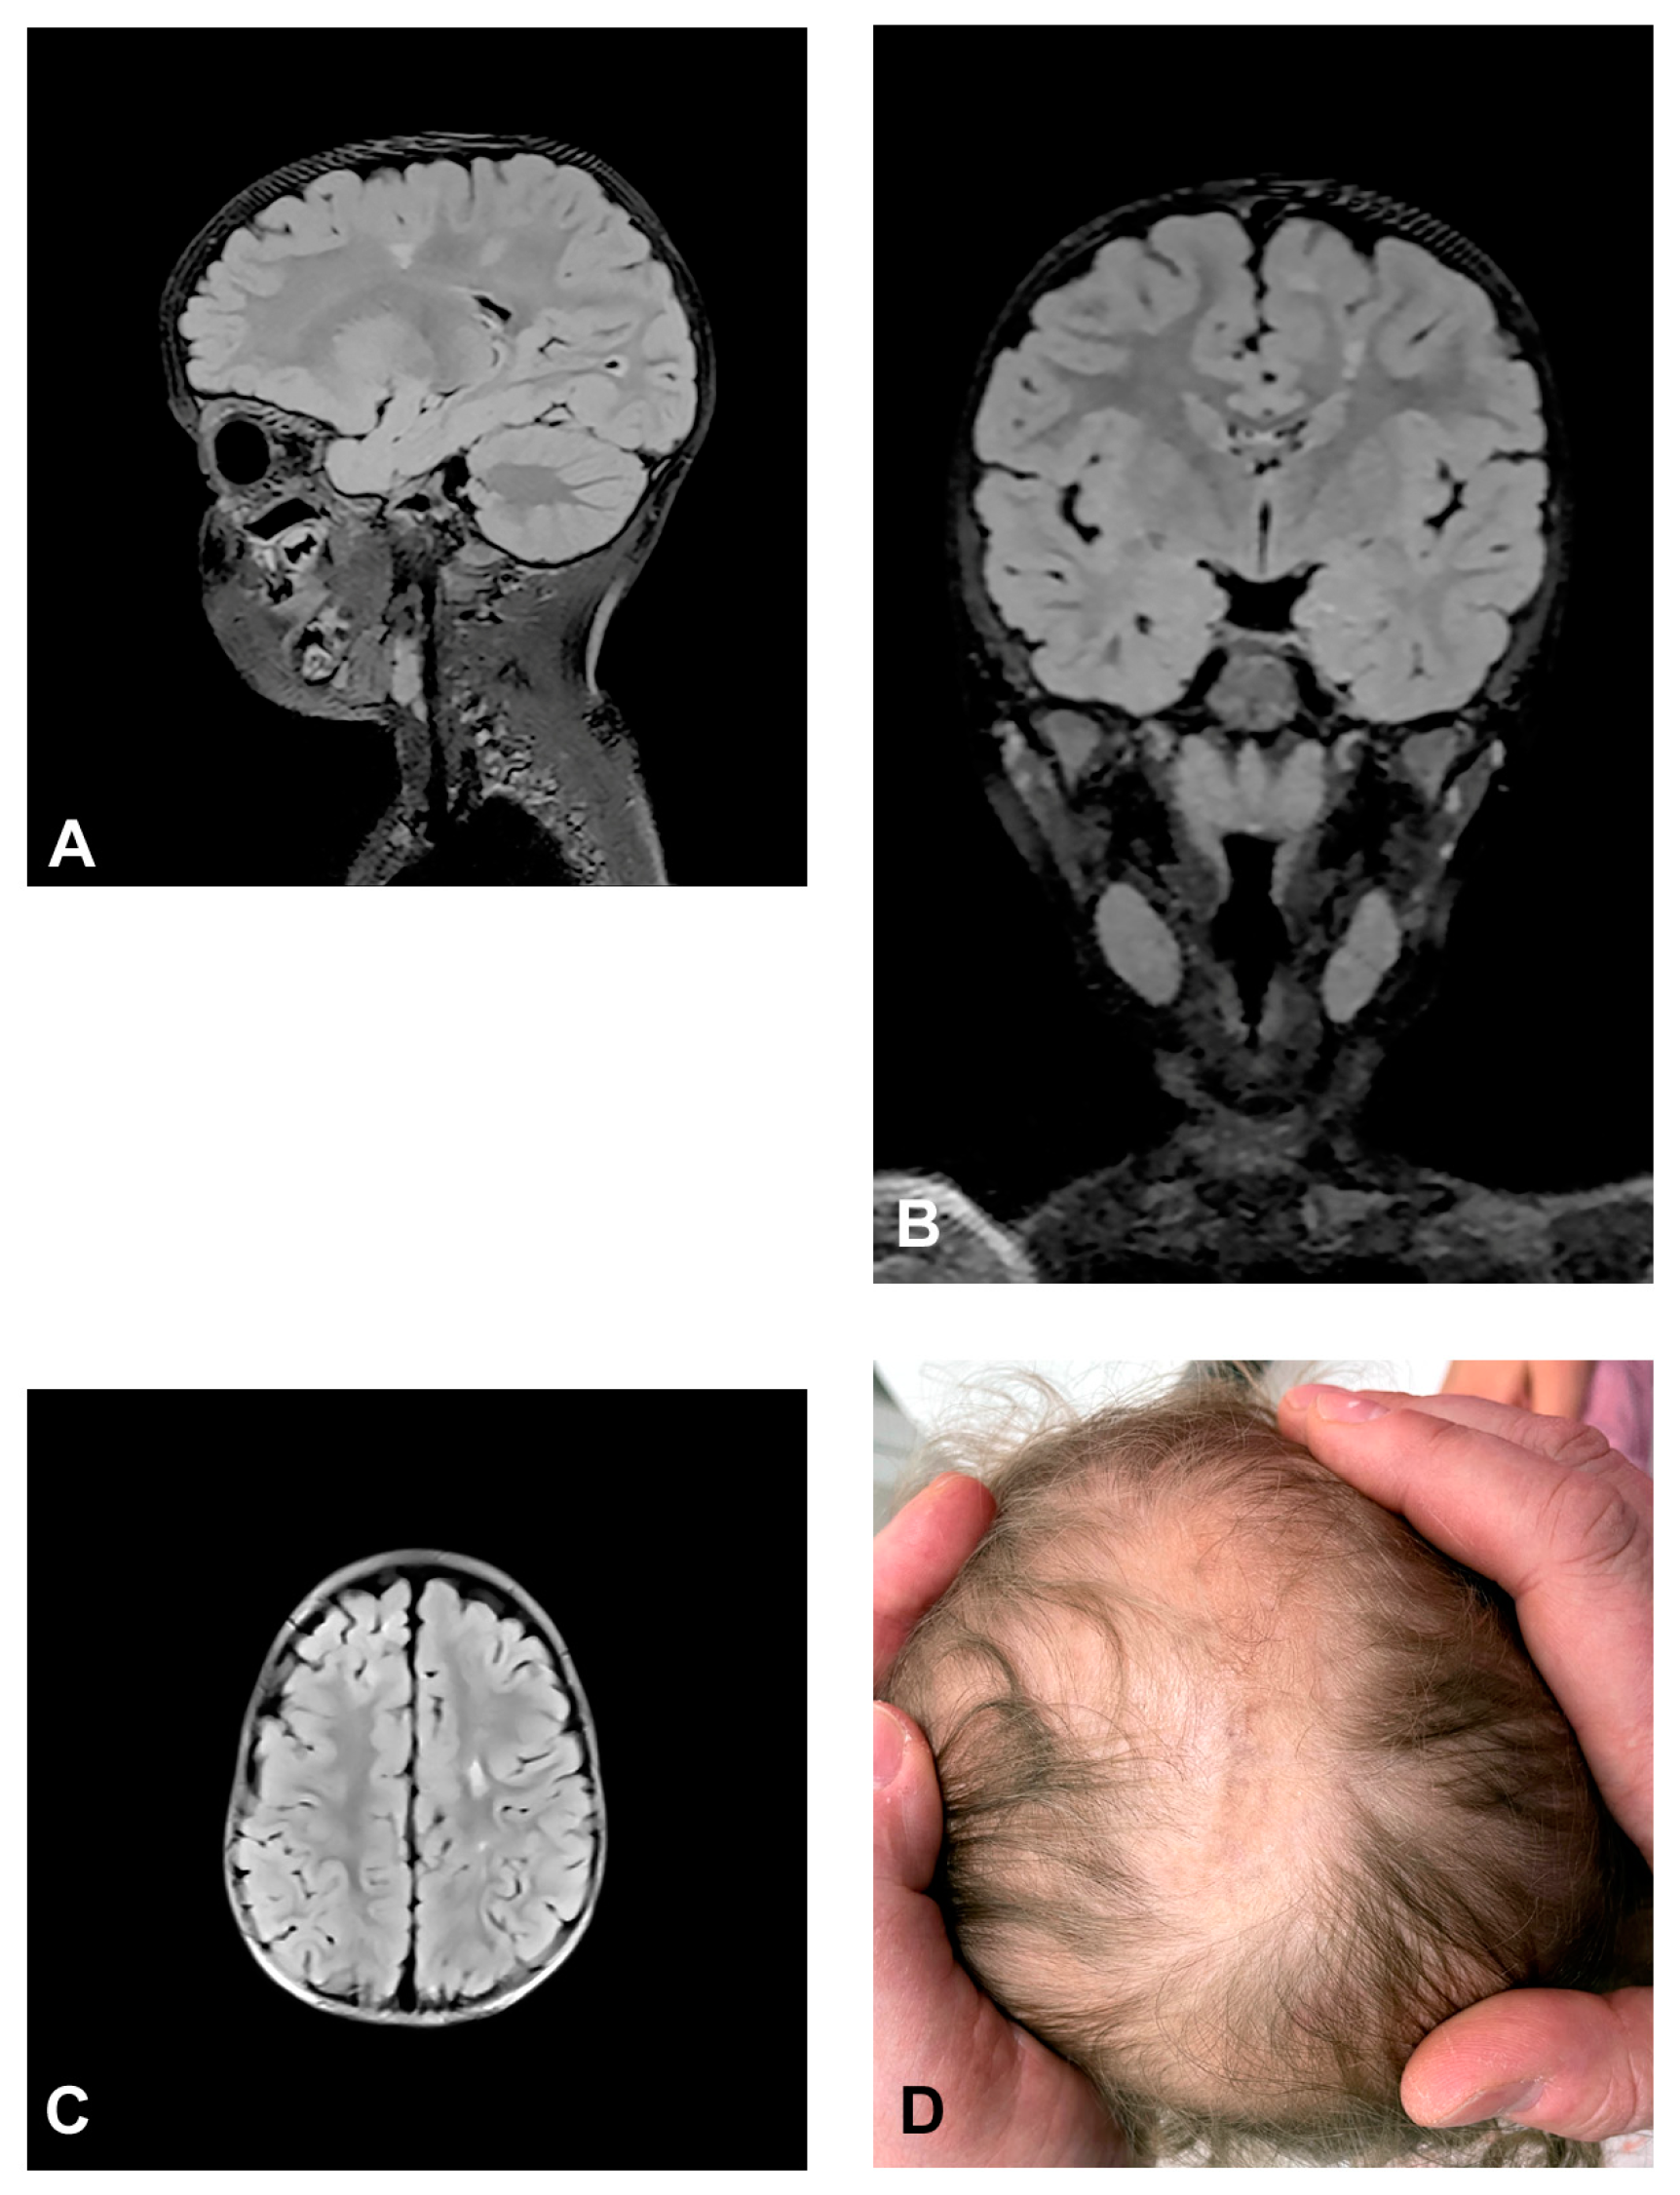

The patient presented stage I and II skin changes following Blaschko lines on the extremities and trunk upon birth. IP skin changes were on the same side of the scalp where small foci of hyperintensities were found using MRI (Figure 3). The patient presented oral anomalies typical for IP, such as gothic palate. Upon neurological examination, there were mildly decreased muscle tones with normal reflexes and motor activity. The patient had mild psychomotor delay, developing unsupported walk from the age of 19 months. She displayed mild speech delay. MRI of the brain showed small foci of hyperintensities, which appeared in a band and triangle-like shape, spreading from subcortical white matter to the left lateral ventricle.

Figure 3.

(Case 3) Sagittal (A), coronal (B) and axial (C) T2 FLAIR magnetic resonance images at the age of 2.5 showing small foci of hyperintensities, which appear in a band and triangle-like shape, spreading from subcortical white matter to the left lateral ventricle similarly to radial migration lines. (D) IP skin changes in the form of Blaschko lines on the same side of the scalp where the small foci of hyperintensities were found.